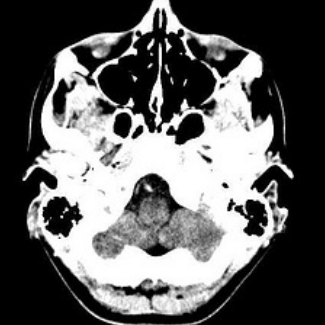

Brain scan

Center for Advanced Neuroimaging (CAN)

As a multidisciplinary center, the Center for Advanced Neuroimaging houses state-of-the-art equipment for various research projects. Faculty, staff, and trainees have expertise in several areas, including psychology, psychiatry, neurology, MRI physics, biology, chemistry, computer science, and engineering.

Xiaoping Hu, director of CAN, and Xu Chen, a research scientist, have been published in several scientific journals on topics such as the effects of intranasal oxytocin on neural activity and testing an MRI-compatible flexible endoscopic robot for neurosurgery.